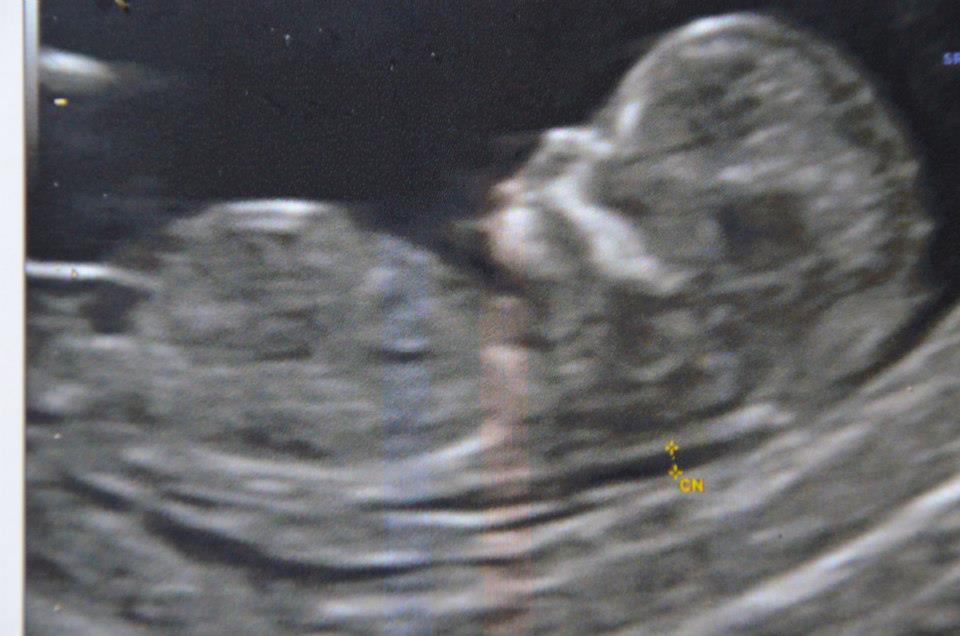

Bon eh depuis c’est sûr hein… Mode Baleine enclenchée pour NuméroBis… Largage prévu début Juin 2013!